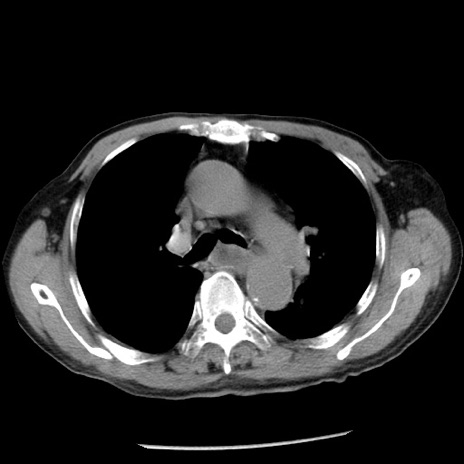

冠状断像

症例26(横断像)

【症例】80歳代男性

【主訴】嘔吐

【現病歴】昨晩2回嘔吐あり、今朝になっても嘔吐あり。来院。

【既往歴】胃潰瘍

【身体所見】意識清明、BT 37.6℃、BP 166/95mmHg、HR 100bpm、SpO2 97%、腹部:平坦・軟、腸蠕動音聴取良好、圧痛なし。

【データ】WBC 21900、CRP 1.46